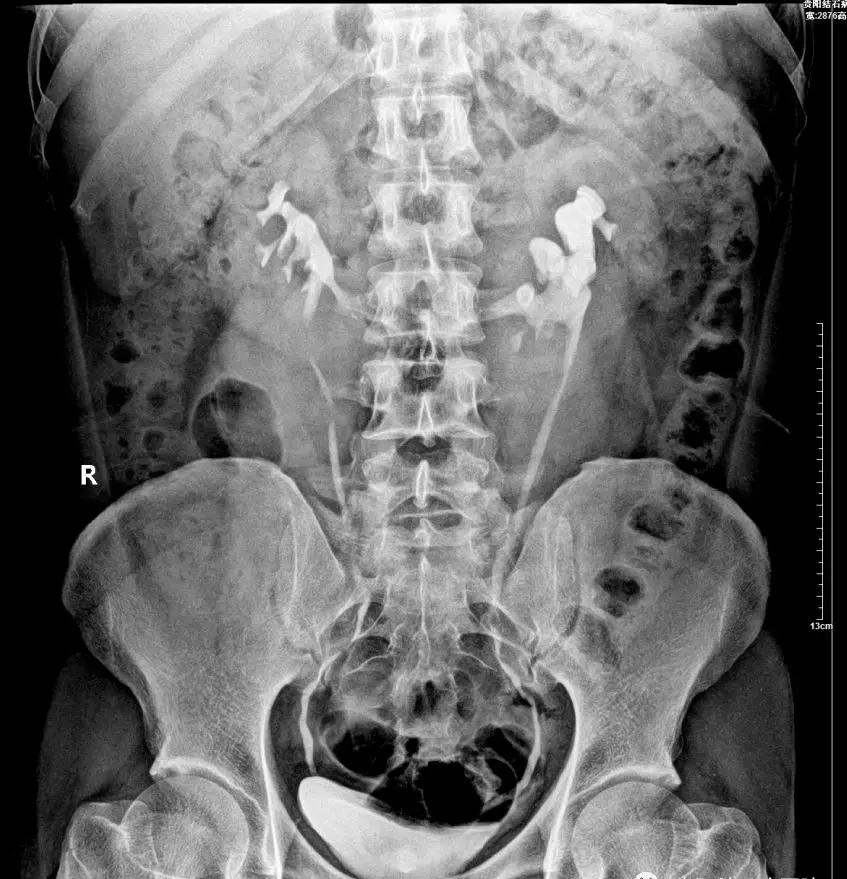

▲贵阳结石病医院为郭先生行静脉尿路造影 确认郭先生的双肾呈现明显的“马蹄肾”形态

与正常人的肾脏相比,马蹄肾的位置比较深,并伴旋转畸形,所以穿刺比较困难 ,但是,医生凭借丰富的手术经验,在泌尿外科医护人员的认真配合下,娴熟开展“ 左侧经皮肾镜碎石取石术 ”,将患者肾盂内数枚3.0x2.5cm的淡黄色的结石顺利去除,手术过程中,患者生命体征平稳,第一期手术圆满完成。